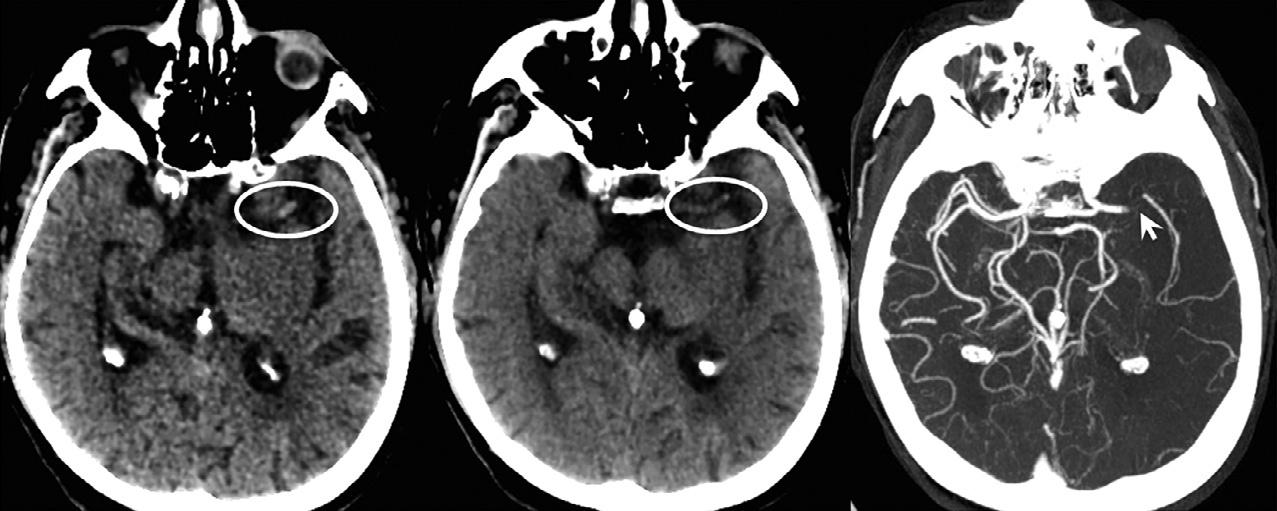

Giventhesepotentiallyverylargeaxialimagingdatasets,imagepostprocessingisrequiredtoefficientlyvisualizevesselabnormalitiesandfacilitatediagnoses (Fig.1.6).Inparticular,maximum-intensityprojection (MIP)imagesoftheintracranialcirculationprovidean easywaytodetectproximalarterialocclusionsinstroke patients,forexample,thatmaybeamenabletocatheterbasedtreatments.TheseMIPimagesdepictthehighest densityalongaparticularimagingray.Forevaluation oftheintracranialarteries,MIPimagesreformattedto 20–30mmthicknesswith3–5mmoverlapcanbecreated inaxial,coronal,andsagittalplanesquicklyatthe scannerconsolebytheCTtechnologist.Morecomplex postprocessingtechniquesincludecurvedreformats, multiplanarvolumereformats,andvolume-rendered images.Curvedreformatsdepicttheentirecourseofa particularvesselinasingletwo-dimensionalimage, andprovideagoodevaluationofarterialsteno-occlusive diseaseintheneck,suchasatthecarotidbifurcation. The3Dvolume-renderedandothersurfacetechniques arelesshelpfulforischemicstrokeevaluation,butare routinelyusedinaneurysmdetectionandtreatment planning(Fig.1.7).

AnearlyCTsignofembolicstrokethatmighthelp guidepatientselectionforintra-arterialclotretrieval therapyisthehyperdensevesselsign(Fig.1.12).More distalclotsinthird-orderbranchesmaybeidentified asdotsigns.Arecentretrospectivestudyshowedthat patientswithCThyperdenseclotlengths > 8mm,as measuredonthin-sectionCT,haveanear-zeroprobabilityofrespondingtoIV-tPAalone;hence,suchpatients mightbenefitfromintra-arterialclotretrieval (Somfordetal.,2002;Riedeletal.,2011;Kamalian etal.,2013).

Fig.1.12. Hyperdenseleftmiddlecerebralarteryclotisvisibleontheaxialthin,1.25-mmcomputedtomography(CT)slice,but onlyasadotsignonthethick,5-mmCTsliceduetopartialvolumeaveraging;confirmedontheaxialCTangiographymaximumintensityprojectionimage.